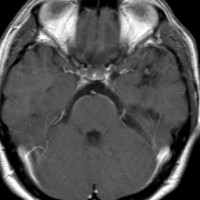

腫瘍から少し出血したために,患者さんはけいれん(てんかん発作)を起こしました。左のT1強調画像では出血を疑います。中央のT2強調画像では海綿状血管腫の周りに脳浮腫があるために白くぼやけた部分があります。右の造影剤を使ったMRIでは造影剤が入るところがほどんど無いことがわかります。側頭葉の海綿状血管腫は側頭葉てんかんという症状で発症することが多いです。